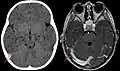

Синус-тромбоз при нативной компьютерной томографии (слева) и МРТ в режиме T1 с контрастным усилением (справа)